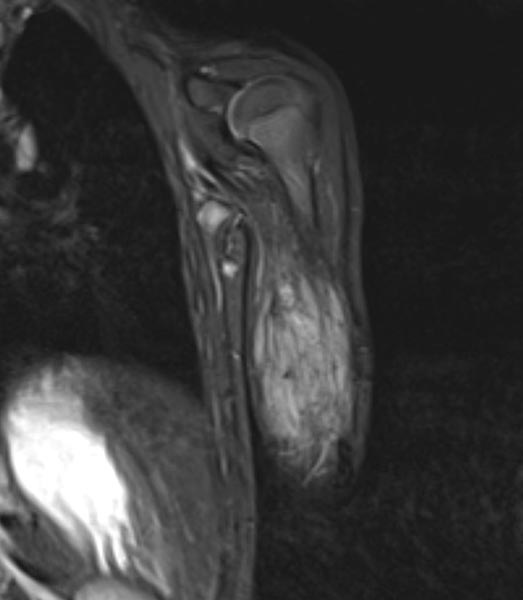

Zur weiteren Sicherung der Differentialdiagnose wird bei dem Kind auch eine MRT durchgeführt. Hier abgebildet eine koronare, T2-gewichtete, fettunterdrückte STIR-Sequenz. Der Tumor ist hier stark hyperintens (weiß im Bild) und scharf zum umgebenden Gewebe abgegrenzt. Er durchdringt alle Gewebeebenen und enthält zentral als Zeichen einer starken arteriellen Perfusion signalfreie Areale, sogenannte Flow-voids.

Zur weiteren Klärung der Differentialdiagnose wurde nochmals eine MRT durchgeführt, hier wieder abgebildet eine koronare, T2-gewichtete, fettunterdrückte STIR-Sequenz. Der Tumor ist jetzt etwas weniger stark hyperintens (weniger weiß), dies spricht für einen etwas höheren Fettanteil in dieser fettunterdrückten Sequenz. Auch die Perfusion hat etwas abgenommen, es finden sich im Vergleich weniger Flow-voids.